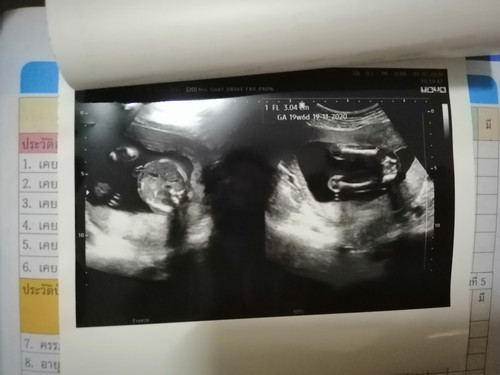

ชาย&หญิง

คุณหมอยังไม่แน่ใจเลยว่าหญิง100%ไหม แม่ๆว่าชายหรือหญิงคะ 19สัปดาห์แล้ว